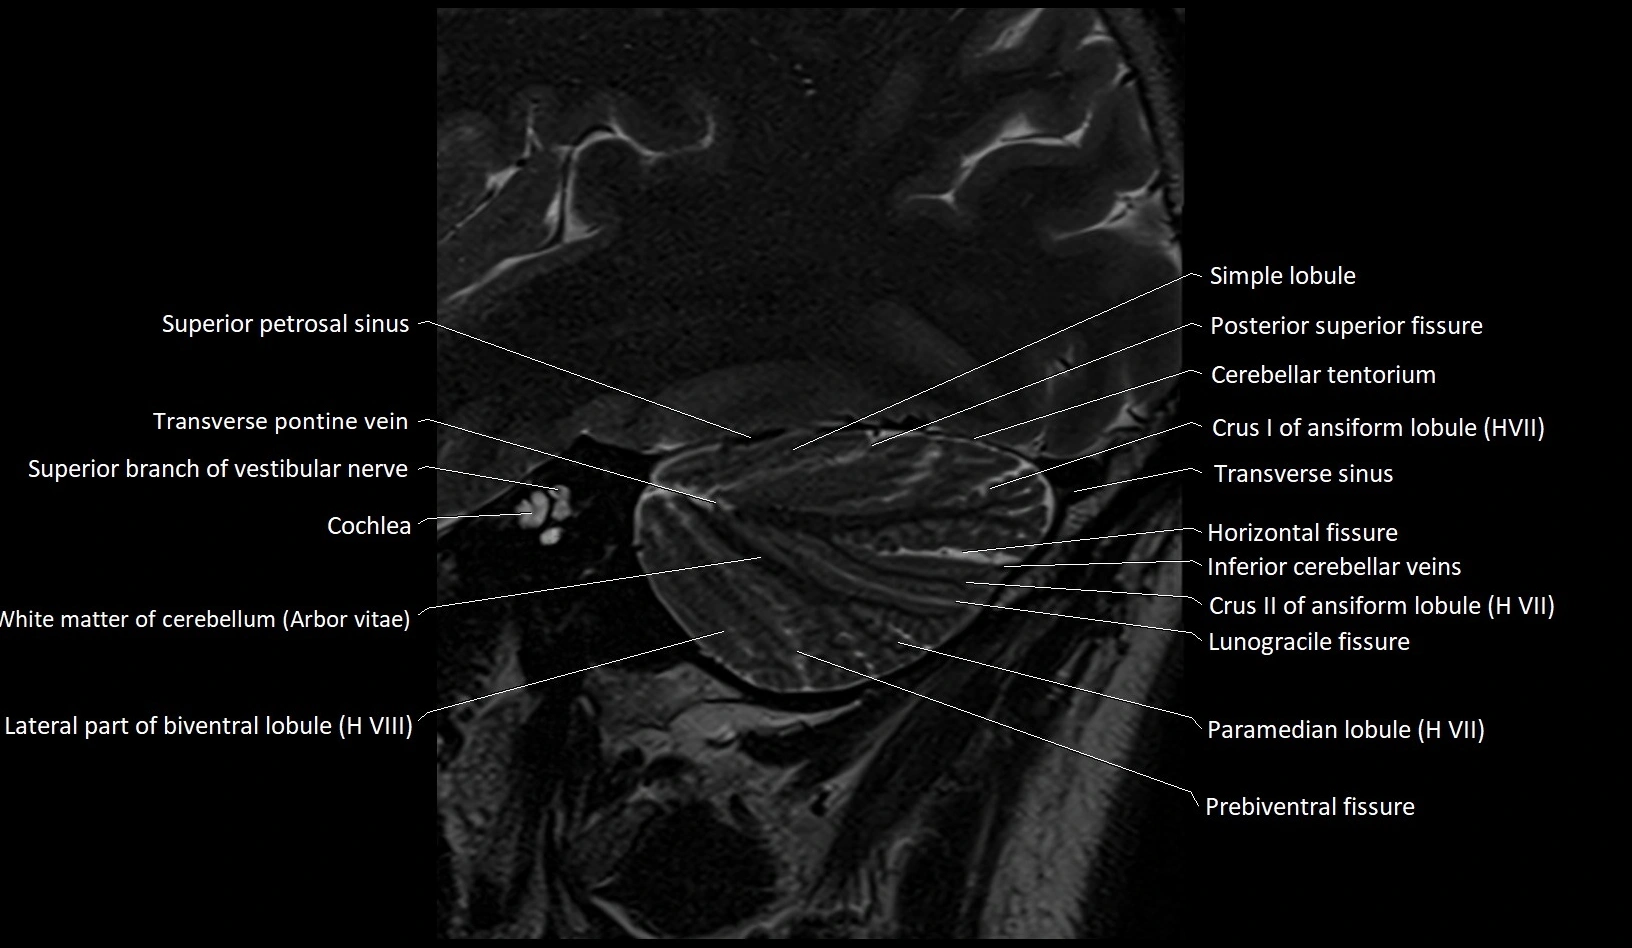

MRI images